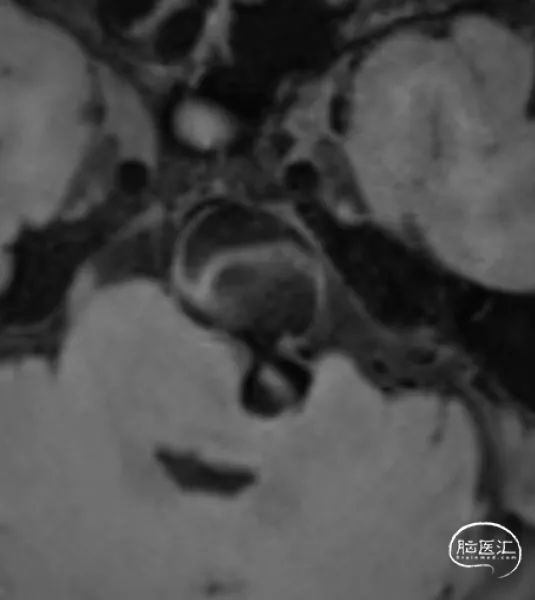

高分辨磁共振

1、该患者属于串联动脉瘤,累及左椎动脉V4段末端和基底动脉近端。其中基底动脉近端为富穿支区域,常规介入治疗面临较高的缺血并发症。

2、血流导向装置可以在尽可能保护穿支的前提下,治疗动脉瘤。而少量弹簧圈填充可以促进动脉瘤愈合。

1、基底动脉瘤介入治疗的主要风险来自于穿支或主要分支受累导致的缺血事件,会导致患者严重致残甚至死亡,围手术期合理的抗栓治疗可以有效对冲此类风险。

3、基底动脉瘤内少量弹簧圈填塞,保护动脉瘤相对薄弱区域,纠正载瘤动脉的喷射血流,减少围手术期动脉瘤破裂风险,促进动脉瘤愈合。